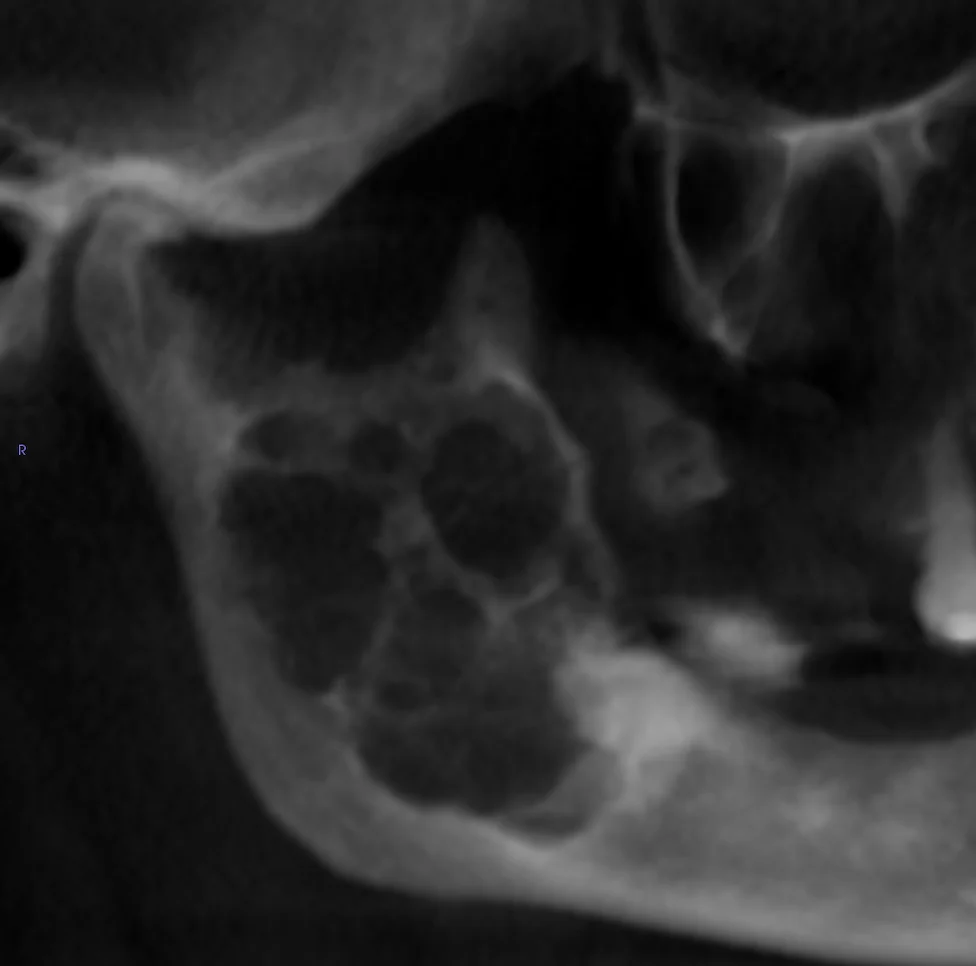

The oral and maxillofacial surgeon plays an essential role in treating oral pathologies, which can include a wide range of conditions affecting the tissues and structures of the mouth, jaw, and face. These pathologies can range from benign tumours to aggressive tumours and even malignant tumours. Early detection and management of certain conditions can have a significant impact on recovery and long-term prognosis. It may happen during a consultation with your dentist or family doctor that they notice an abnormality and are concerned about its nature. They will then send a consultation request for one of the surgeons on our team to examine you. After a thorough evaluation of the different structures of the face, oral cavity, jaws, and neck, and in some cases, taking x-rays, a biopsy may be necessary. A biopsy involves taking a tissue sample that is submitted for microscopic analysis by a pathologist. This can then help establish a treatment plan ranging from simple regular follow-ups to surgical treatment.